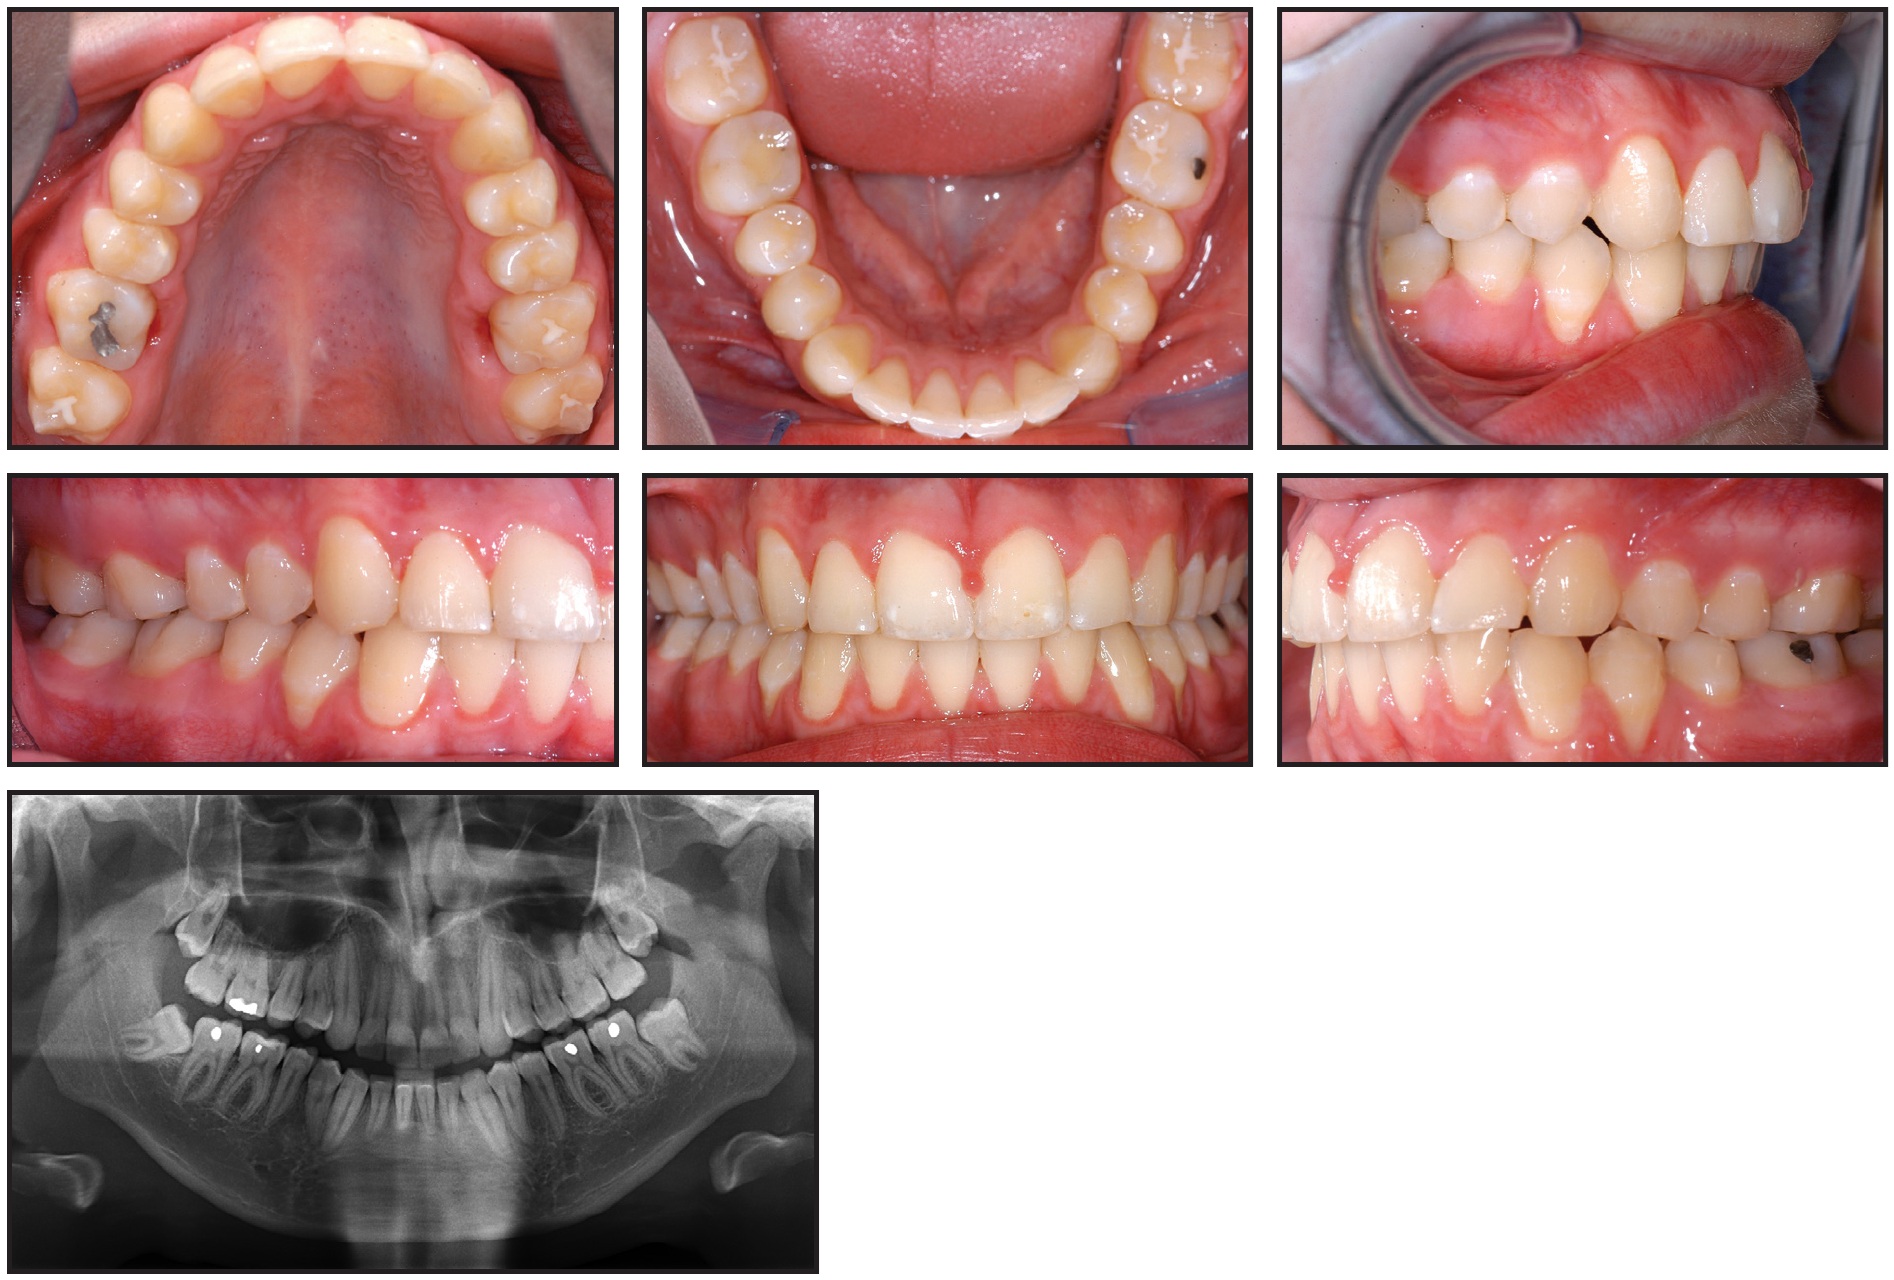

After two years of treatment, both lower molars were upright, and a stable occlusal relationship to the upper molars was achieved (Fig. 8).

Fig. 8 Case 2. After two years of uprighting, showing good angulation and positioning of lower third molars.